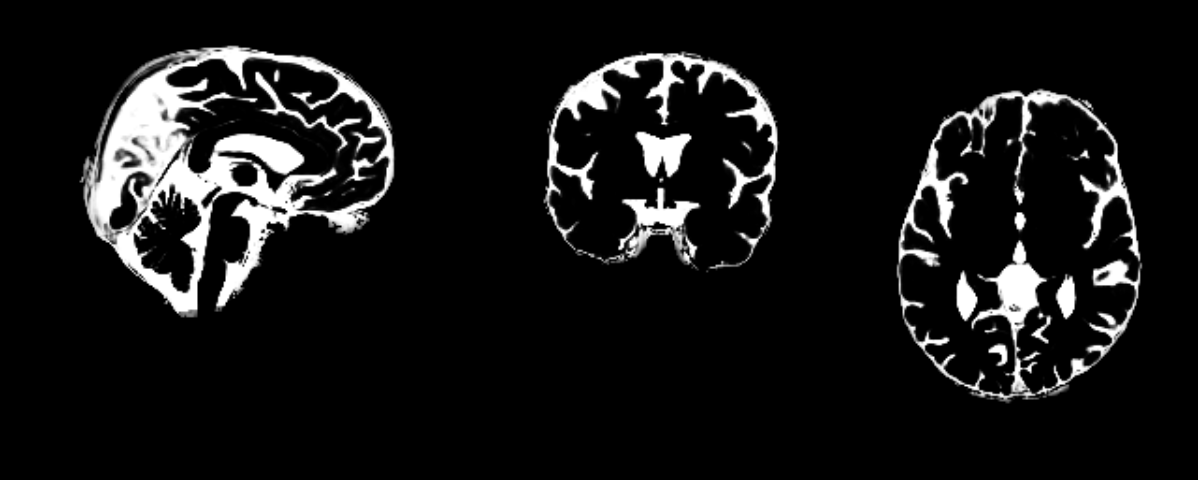

The usual FSL/SPM style CSF mask covers the entire brain. I have attached a snapshot as an example. Conn uses SPM segmentation mask by default for each subject. The attached file is the partial volume map; this would be binarized and eroded before time series extraction for regression during denoising.